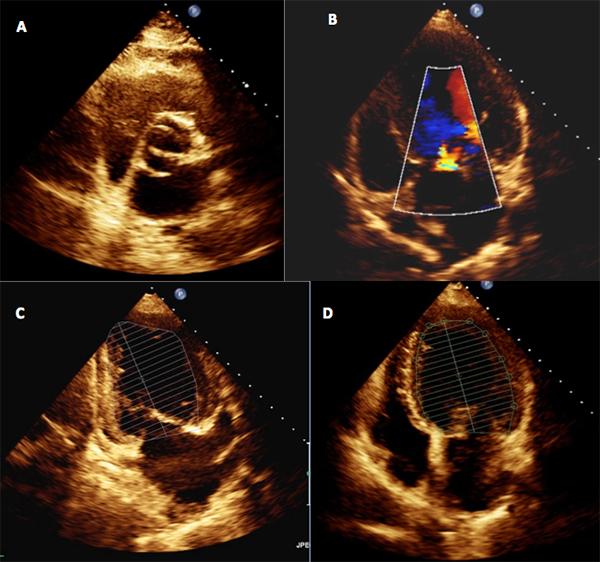

Interrupted aortic arch (IAA) is a rare congenital abnormality with only a few cases reported in adults. It is defined as complete loss of continuity between the ascending and descending portions of the aorta, and is usually associated with other cardiac defects. The diagnosis in adults should be suspected in the presence of refractory hypertension, a careful physical examination being crucial to early diagnosis. Magnetic resonance angiography (MRA) techniques can accurately characterize cardiovascular anatomy, and also provide information regarding heart chamber and valve function.

Although rare, interrupted aortic arch (IAA) must be considered in the differential diagnosis of adults with refractory hypertension. A careful physical examination, with evaluation of femoral pulses and blood pressure in the four limbs, is essential for the diagnosis and for ensuring that the correct diagnosis is made promptly.This case highlights the value of magnetic resonance angiography (MRA) in radiation-free non-invasive evaluation of adults with congenital aortic abnormalities, as it may provide clinically important haemodynamic information.Only a few cases have been reported in adults. We present an unusual case in which the diagnosis was not made until adulthood.